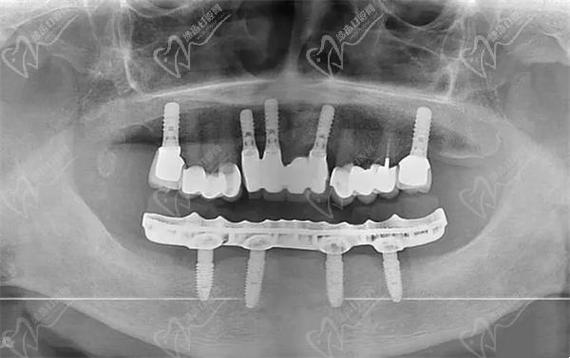

是以选择四颗种植体还是六颗种植体,关键取决于骨量状况以及咀嚼力方面的需求。All-on-4技术于后牙区域运用倾斜植入的方式,避免上颌窦亦或是下颌神经管,适宜骨量呈现轻度萎缩情形的患者。然而四颗种植体分散咬合力这一能力较为弱些,要是喜爱食用硬物亦或是存在夜间磨牙的情况,那么可能增加植体所承受的负荷。All-on-6在磨牙区会额外多植入两颗植体,受力更为均匀,适合骨量充裕或者对咀嚼效率有着较高要求的人群。临床所获取的数据表明,六颗方案长期的成功率略微高一点,但是手术的复杂程度以及费用也会相应地有所增加。

在生物力学层面来看,对于半口修复来讲的话,起码得要有4颗种植体方能稳定地去支撑连桥牙冠。要是骨量极其差并且没办法进行植骨的情况,能够采用穿颧种植这个方式,或者是选择2颗植体加上两端延伸的那种“悬臂桥”,不过后面这种方式失败的风险是比较高的,仅仅是当作一种妥协的方案。实际上标准答案是这样的:正常的状况下种植4颗,要是追求更加耐用的状况就选择6颗。需要注意的是,种植体的数量并非是越多就越好的,数量过多的话会损伤健康的骨组织,而且会增加清洁的难度。医生会借助CBCT三维测量骨的高度、厚度以及神经所在的位置,从而精确地规划植入的位点。